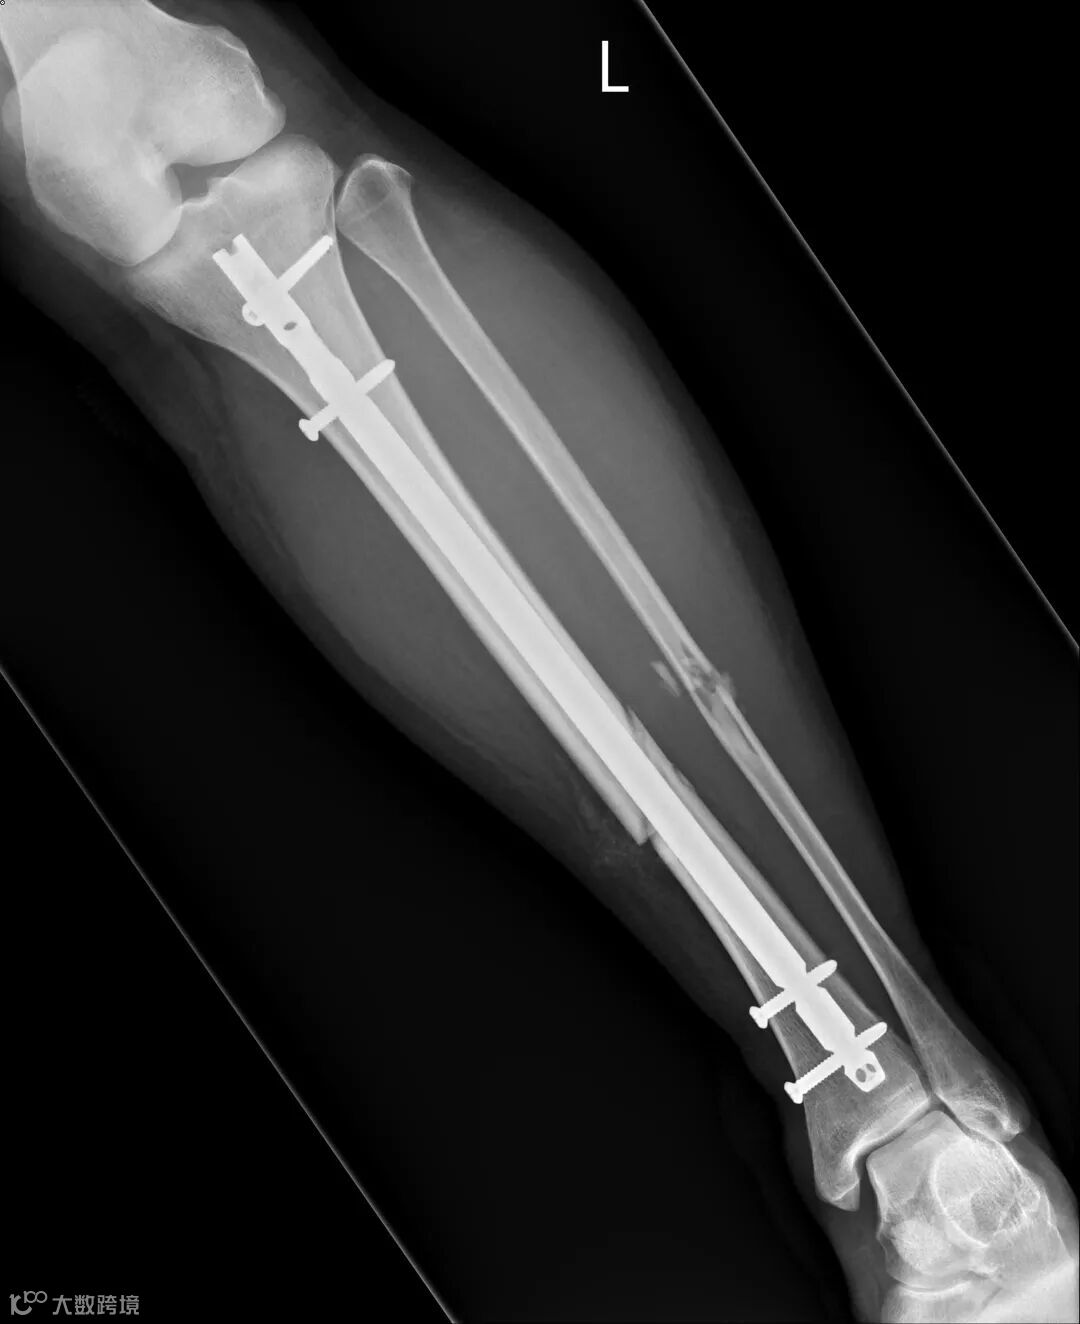

“这是骨折变形了。”

后来看到我的病历上写到,据EMT表示患者为机汽车事故,有着安全帽,到场时患者趴在地。左小腿触痛、肿胀、变形。不记得车祸发生路线,疑似失去意识。

我不知道有没有事,从车祸发生当下开始,只能静等医护人员安排。X光室门开启,变形小腿摆拍酷刑开始。从病床移动到摄影台,放射师用辅具帮小腿摆好几个不同拍摄角度。只要一点移动,就产生剧烈疼痛,我在心里重复默念:“痛,只是种感觉。”

医生告知诊断:小腿里两根骨头都断了,要用手术固定。小腿里有两根骨头,胫骨和腓骨。他们的排列像吃鸡翅时,掰开的那大小骨头。

姐姐国中同学刚好是骨科住院医生,特地过来关心,耐心地说明目前伤势,除了已知的小腿骨折外,他指着脚背说,这里也有骨折。

我马上说出骨头学名:跖骨,因为同一只脚第四根有断过。

复健科医生看到X光片后都说:“你这个很严重耶。”为了想尽快恢复生活,我积极去复健治疗。因长时间卧床,受伤腿肌肉严重萎缩,努力运动,抵挡肌肉流失的速度。